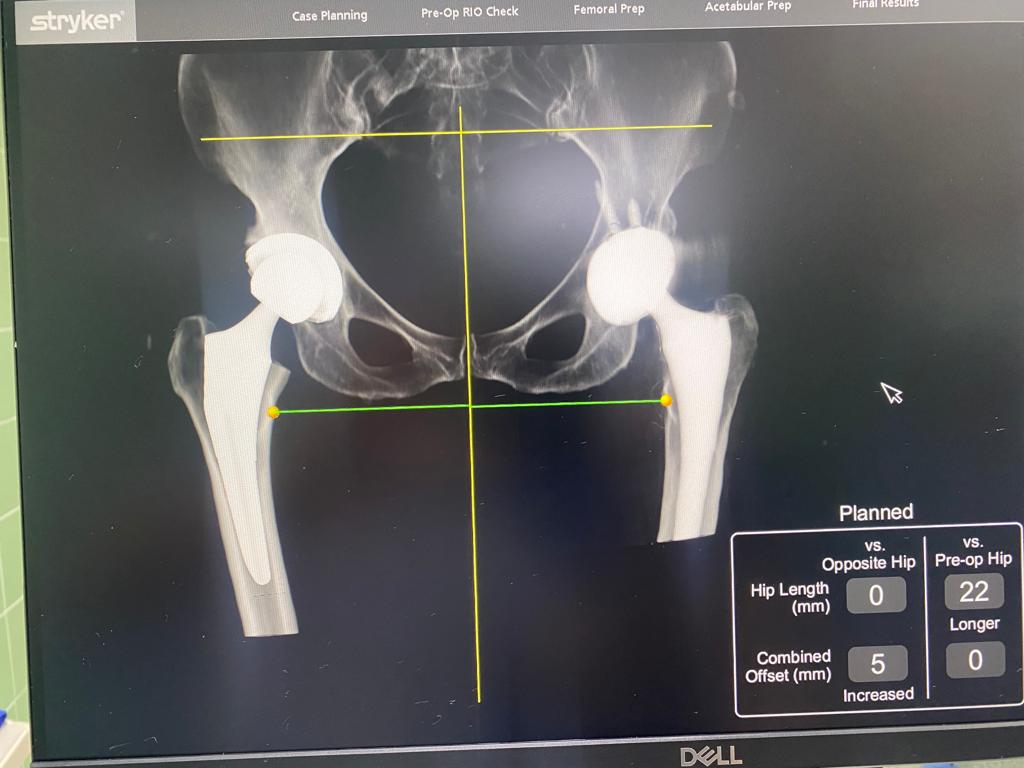

Robotik kalça protezi, geleneksel kalça protezlerinin ötesine geçen bir teknolojik gelişmedir.  Ameliyat sırasında kalça ekleminin etrafına yerleştirilen bir takım sensörler yardımıyla kişinin anatomisi robota tanıtılarak robot yardımlı bir protez cerrahisi yapılır. Robotik kalça protezleri, cerrahi sırasında sağlanması gereken bir takım kemik ve yumuşak doku dengelerinin robot yardımıyla yapılabildiği böylece daha mükemmel ve hatasız bir protez uygulanabildiği cerrahi bir tekniktir. Böylece hastaların daha iyi bir denge, koordinasyon ve hareket yeteneği kazanmalarına yardımcı olur.

Diğer yandan özellikle kalça protezlerinde protezin asetabuler (Yuva) ve femoral (uyluk) tarafta yanlış yerleştirilmesi protezde oluşan çıkıklara , protezin erken gevşemesine , bacak eşitsizliklerine neden olabilir. Robotik kalça protezi sayesinde protezler mükemmel konumda ve açıda yerleştirildiği gibi bacak boyu milimetrik olarak karşı tarafla eşitlenir. Yine protezlerin yerleştirilmesi ,yerleştirme öncesi yapılacak oyma işlemleri de robot yardımıyla yapıldığından protezlerin boylarının seçimi ve konumlandırması doğru yapılabilir. Bu özellikler kalça protezi olan hastanın klinik iyileşmesini doğrudan etkileyeceği gibi fonksiyonel kapasitesini de arttırır. Ayrıca doğru konumlanmış protezin ömrü daha uzun olacaktır.

• Hem asetabuler hem de femoral taraf protezlerinin ideal pozisyonda yerleştirilmesi kalça protezleri sonrası görülen çıkık itimalini oldukça azaltır.

• Kalça protezi sonrası görülebilecek bacak eşitszilği ihtimalini en aza indirir.